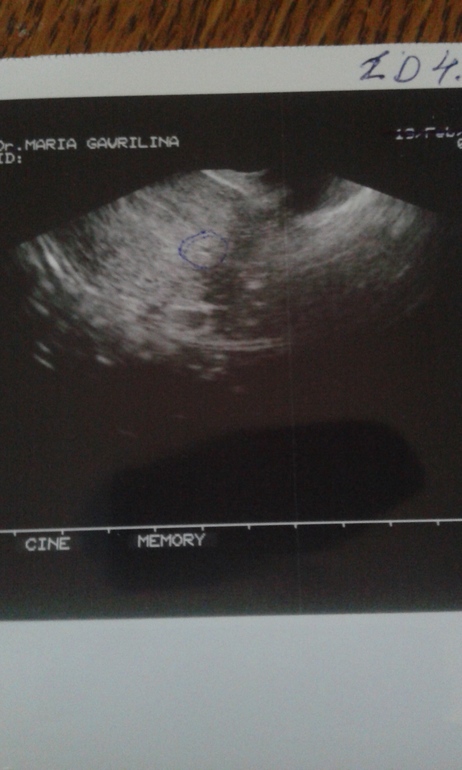

мои родненькие,вы поймёте и поддержите.может кто то проходил уже через всё это.итак ,помните мой тест в воскресенье? большинство поздравляли,но кое кто упорно мне доказывал что это реагент.в понедельник начались М,немного странны.коричневые,но по объёму обычные.и меня терзали тянущие боли в области ПЯ.хгч в понедельник был 0.678 мл,то есть отрицательный.сегодня поехала к Г взять лекарство ,которое она мне привезла из Бельгии.попросила её глянуть меня на узи,по поводу болей.вот снимок смотрите сами.(ниже).матка увеличена,эндометрий беременный,яичники пустые(никаких фоликулов к след циклу не зреет).повторный анализ на хгч отриц.в матке скопление крови.колем окситоцин 5 дней по ампуле,потом контроль узи,если ничего не поможет,то чистка.боже,что случилось то.почему?